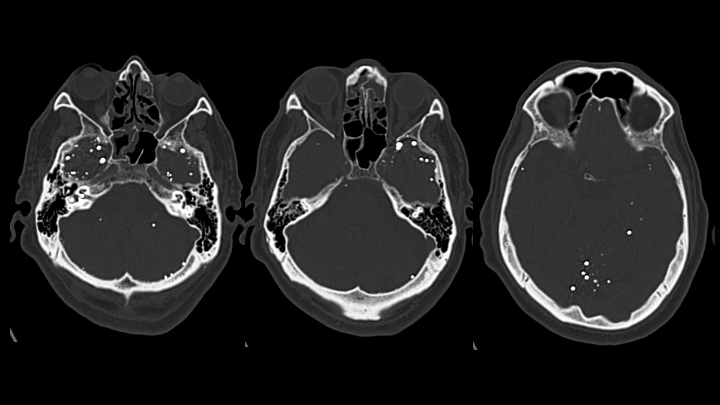

Se observan múltiples pequeños focos de material hiperatenuante dispersos en los espacios de circulación del LCR en la base del cráneo (localización extraaxial).

Se identifican múltiples pequeñas hiperdensidades intratecales, de tamaños variables.

El material presenta densidad metálica y genera artefactos en estría (streak artifacts).